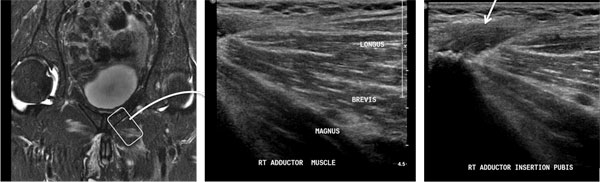

Groin Pain

One of the spezialized areas in our division is the diagnosis and treatment of groin pain with MRI and ultrasound.  More information...

We are one of the few centers in the country to provide a full range of diagnostic musculoskeletal ultrasound. Ultrasound is an effective guide for procedures such as dry needling/tenotomy/injection /aspiration of joints, bursas, ganglion cysts, muscles and tendons; treatment of "sports hernia," tennis elbow, plantar fasciitis, calcific rotator cuff tendinitis and other chronic conditions.